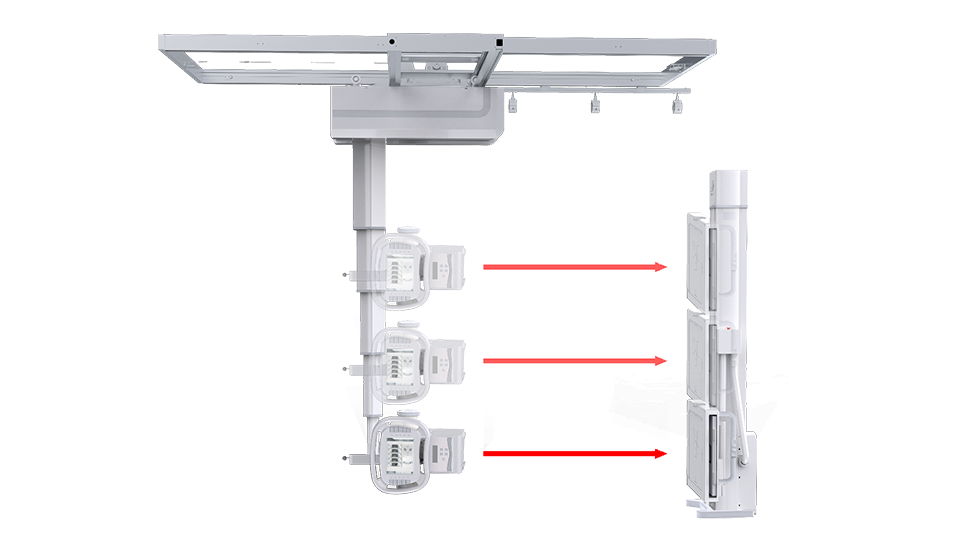

● 手动电动一体化

悬吊配备手动模式与电动模式,沿天轨横纵移动时可选手动或电动,满足不同医护人员使用习惯。